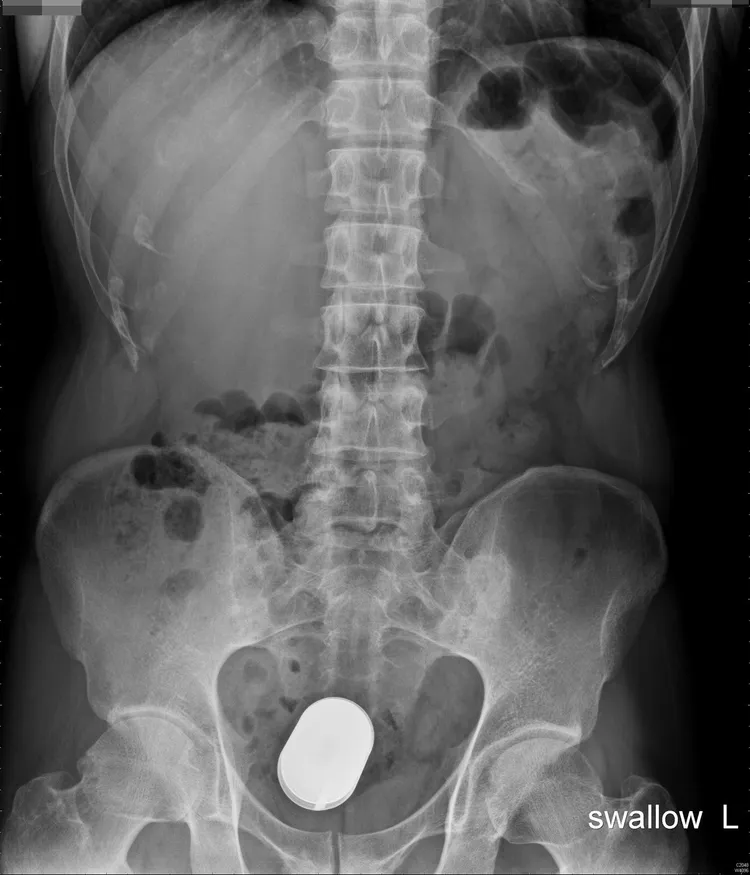

收治男子的高雄長庚醫院大腸直腸外科主治醫師蔡鎧隆表示,男子走進急診室自述剛與朋友喝酒,朋友塞了顆電池到他的肛門,醫護隨即為他安排X光檢查,一顆一號的大電池就在男子的肛門裡。

蔡鎧隆接著戴上手套,但不管是徒手或以內視鏡伸進,都因男子太緊張,肛門括約肌收縮,電池一再在男子體內滑掉,拿不出來,因此,他決定在開刀房裡,讓男子在全身麻醉下,再取出這顆電池。